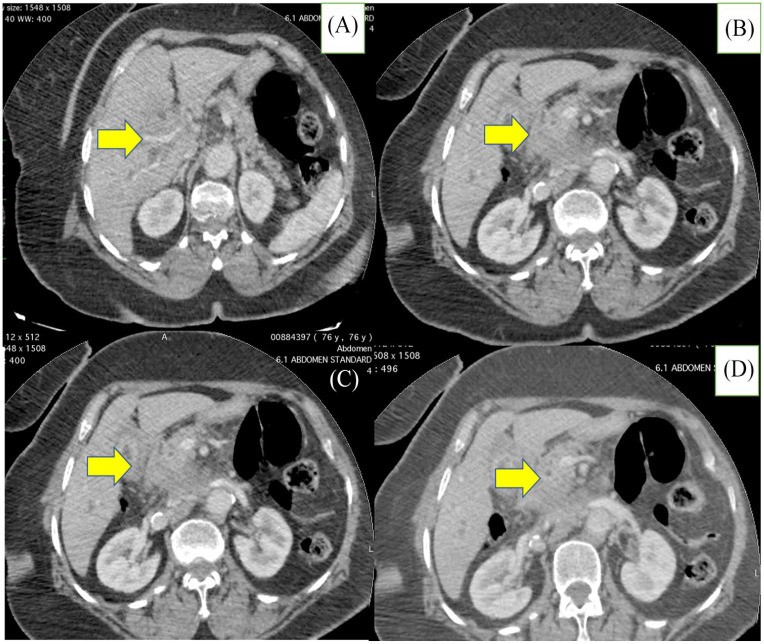

Biliary tract carcinomas (BTC) are malignant epithelial neoplasms subdivided anatomically into: gallbladder carcinomas and carcinomas of the bile duct or cholangiocarcinomas (CCA); including intrahepatic, hilar/perihilar, and distal CCA. Adenocarcinoma accounts for the most common BTC (over 90% of all carcinomas), while other histological subtypes represent rarer forms including: poorly cohesive/signet ring cell carcinoma, which has a greater malignant potential than conventional BTC and a poorer prognosis. Only few cases have been reported in the literature to date. The positive diagnosis remains on histology. Herein, we describe a new case of poorly cohesive carcinoma of bile duct extending to the gallbladder in a 60 years old women with a fatal outcome, to raise awareness of this rare entity and to provide data for larger series.